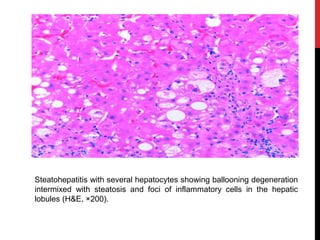

Steatohepatitis with several hepatocytes showing ballooning degeneration

intermixed with steatosis and foci of inflammatory cells in the hepatic

lobules (H&E, ×200).